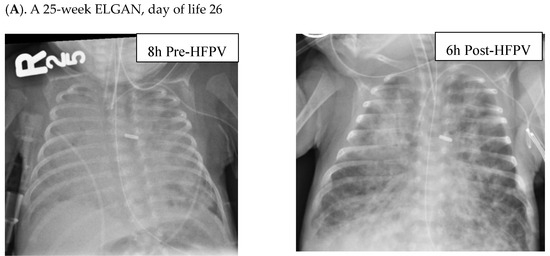

Radiographic improvements were seen in ELGANs, with a representative series shown in Figure 2.

Figure 2.

Radiographs of ELGANs placed on HFPV. Patient (A) is a 25-week gestation infant who was found to have worsening diffuse atelectasis with almost complete opacification of lung fields on a chest X-ray taken 8 h prior to placement on HFPV on DOL 46. Within 6 h after being placed on HFPV, the infant had a dramatic improvement in his clinical status with decreased FiO2 requirements and improved findings on CXR as (shown on the right). Patient (B) is a 25-week gestation infant changed to HFPV on DOL 46. CXRs performed 2 days prior, and 8 and 40 h post-placement on HFPV revealed a more gradual clearing of opacified lung fields. Patient (C) is a 26-week gestation infant with shifting areas of atelectasis, who was changed to HFPV on d186 (left). CXRs 8 h prior to placement on HFPV and 15 h following HFPV, respectively, revealed shifting and then improved aeration.